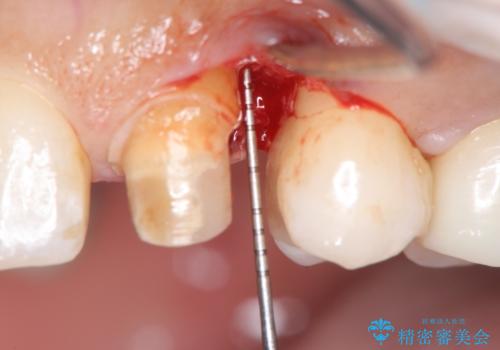

- 左上犬歯の一部が歯ぐきの中まで虫歯になっており、部分矯正をして歯を引っ張り出しました。(エクストリュージョン)

その後、手術をしてしっかり骨の位置を修正し、歯を引っ張り出した時に増殖した余分な歯ぐきを薄くする歯周外科治療も行なっています。

左:虫歯を除去したところ。遠心が歯ぐきより深い状態です。中:そのままかぶせようとすると、遠心が歯ぐきが腫れやすい状態です。右:エクストリュージョンをしたことで、遠心の歯ぐきの腫れが収まっていることがわかります。